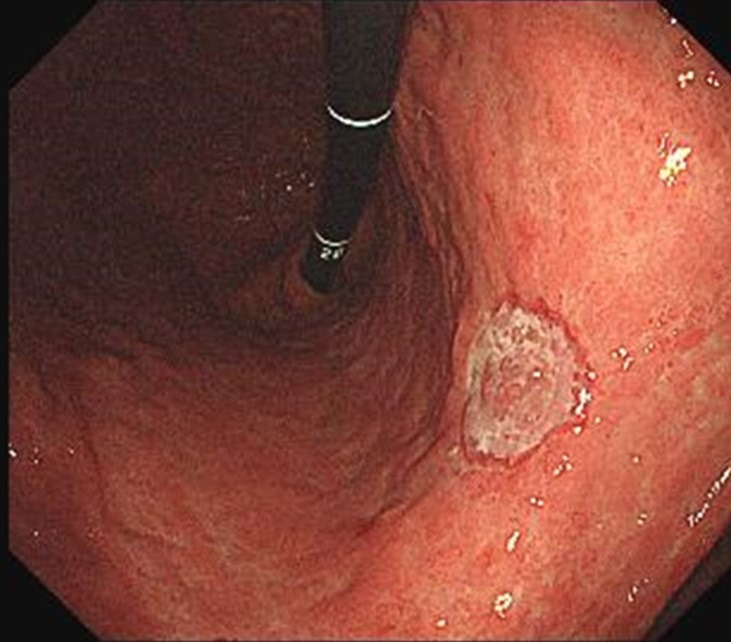

미란·궤양의 변성 여부 평가

겉으로 보기에는 단순 궤양이지만 실제로는 악성 궤양의 형태인 경우가 있어, 의심 부위에서는 조직검사가 필수입니다. 특히 경계가 불규칙하거나 두꺼워 보이는 궤양은 초기 암일 가능성을 배제하기 위해 반드시 세포 검사가 이루어져야 합니다.